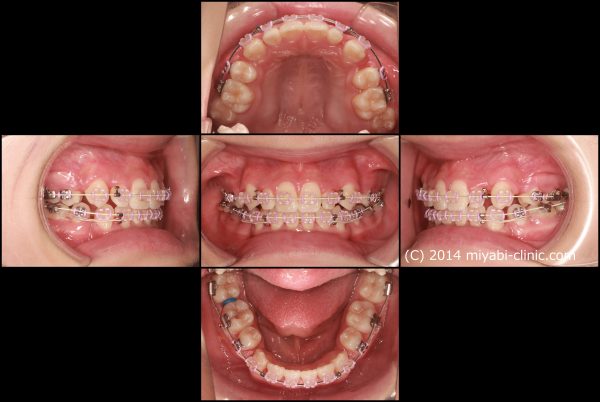

「 八重歯を 治してほしい」 21歳 女性 治療期間19か月(上下顎叢生)

21歳の 女性です。

「 八重歯を 治してほしい 」との事で来院されました。

典型的な ”八重歯” の状態です。

犬歯(中心から3番目の歯)が外に飛び出しています。

この犬歯の影響で口内炎が絶えないのが悩みとの事です

これだけ出ていると唇が常に擦れますよね・・・ お辛いと思います

前歯 4本のうち、2本が 逆に噛んでいます

上の八重歯に目が行きがちですが、下の歯ならびも、乱れた状態ですね

犬歯の唇側転位を伴う 上下顎叢生です

八重歯と 口もとを治すために上下顎左右の小臼歯抜歯を行い、前歯を整列しました。

2022年11月28日にスタートして 、2024年5月25日に 終 了 しました。

治療期間は19か月でした。

小臼歯の抜歯を行ったことで 犬歯の飛び出しが整い、

前歯は整列し八重歯はすっかりと解消しました。大きすぎた歯ならびが適正になりました。

上だけ注目されがちですが、下あごも前歯が整列し歯ならびが整いました。

また、前後的な距離が短くなり、適正な長さになりました。

上下の顎が適正な長さになった、この効果で上下の前歯が下がりました。

治療前後で前歯の傾斜、八重歯の飛び出しがかなり改善しました。